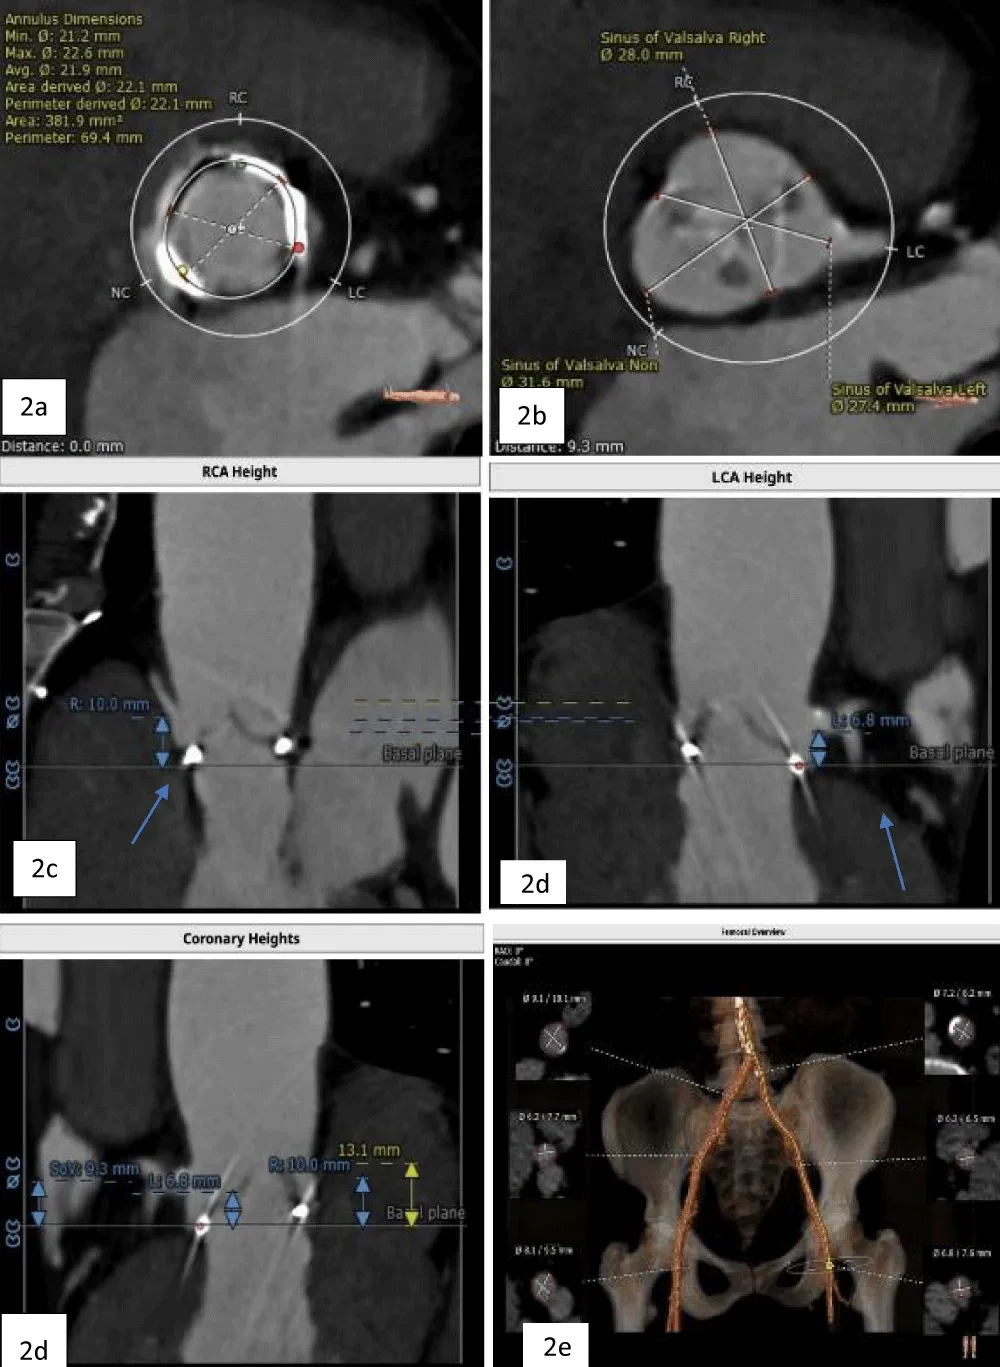

The patient’s past surgical notes were traced, which revealed that the initial AV replacement was performed using a 21 mm CROWN PRT™ stented bioprosthetic valve (LivaNova PLC, London, United Kingdom). Since the patient had high EuroSCORE II and STS scores, the Heart Team selected TAVI. Following the pre-TAVI screening, her coronary angiogram revealed non-obstructive lesions in the left anterior descending (LAD) artery. The 2-D contrast-enhanced CT and aortography revealed an average aortic annulus diameter of 21.9 mm, annular area of 381.9 mm2, and annulus perimeter of 69.4 mm, as seen in Figure 2a. The sinus of Valsalva (SOV) diameters of the left, right, and non-coronary cusps were 27.4 mm, 28 mm, and 31.6 mm, respectively (Figure 2b). However, the right and left coronary ostial (LCO) heights were 10 mm and 6.8 mm, respectively, both being abnormally low including the critically short LCO that was well visualized on CT (Figure 2c,2d). The SOV height was 9.3 mm and the height of the sino-tubular junction (STJ) was 13.1 mm (Figure 2e), while the average diameter of the STJ was 28.2 mm. In terms of access, both the femoral and iliac arteries had acceptable diameters on both sides without severe calcification showing suitability for a transfemoral approach (Figure 2f). On 2D-CT, the predicted VTC distance was 6.7 mm for the right coronary ostia (RCO) and 4.1 mm for the LCO, if a 21.5 mm Myval THV was used (Figure 3). The 21.5 mm BE Myval (Meril Life Sciences Pvt. Ltd., Vapi, India) was selected to be deployed under rapid pacing.

Figure 2: a. Annular dimensions b. SOV diameters of the left, right, and non-coronary cusps c. Heights of the LCA (6.8 mm) and RCA (10 mm) (blue arrows) d. Showing height of SOV (9.3 mm), and e. The diameters of the iliofemoral artery at the access site.